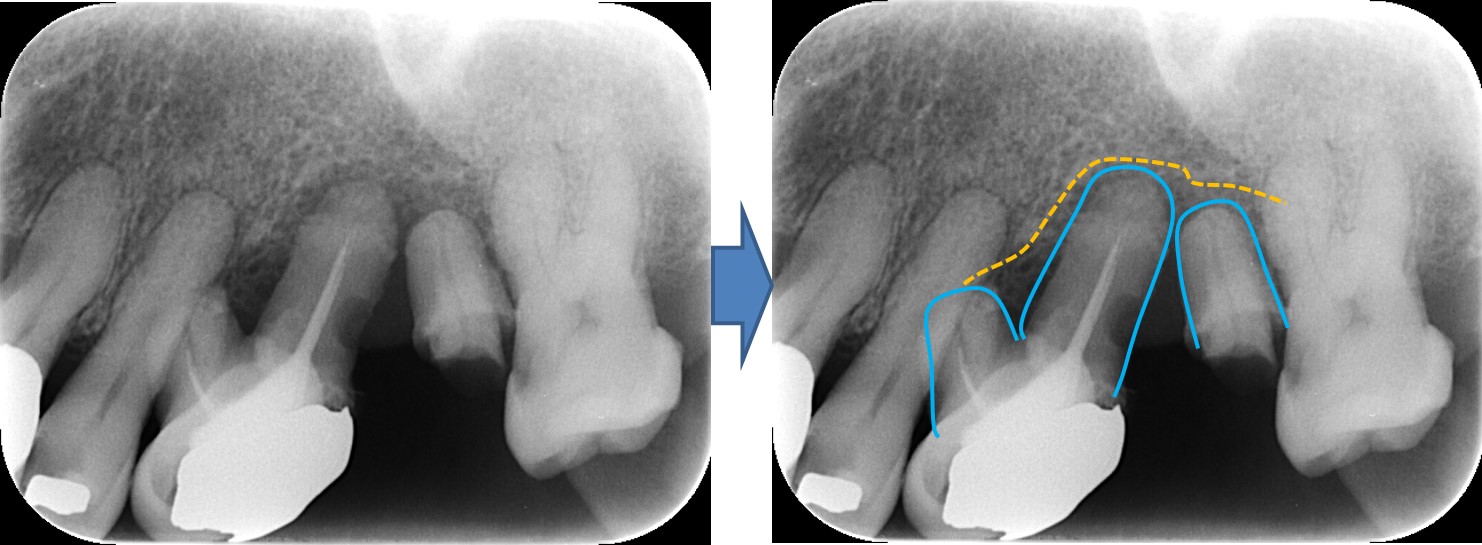

← 195.歯の移植